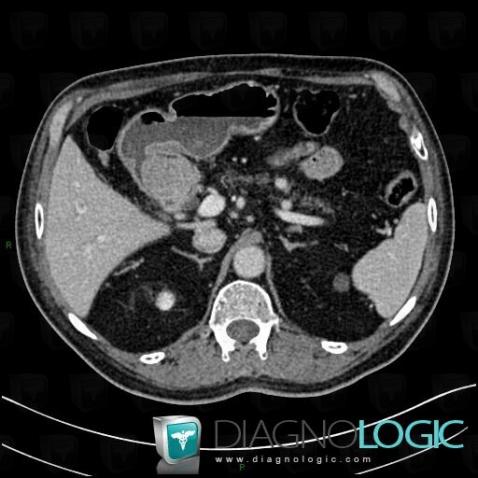

Duodenal adenocarcinoma, Duodenum, CT

Here is the specific information in the key image above:

- Diagnosis Duodenal adenocarcinoma, Location(s) Duodenum, with gamuts Duodenal mass or filling defect